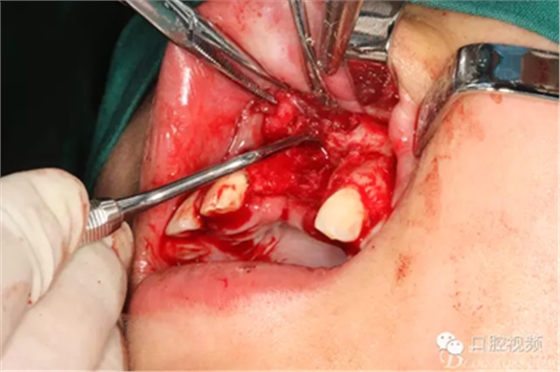

圖10.摘除死骨、并刮除周圍炎性肉芽組織。

圖11.球鉆修整牙槽骨面。

圖12.繼續(xù)清理創(chuàng)面周圍炎性組織

圖13. 清理、沖洗完畢的創(chuàng)面情況